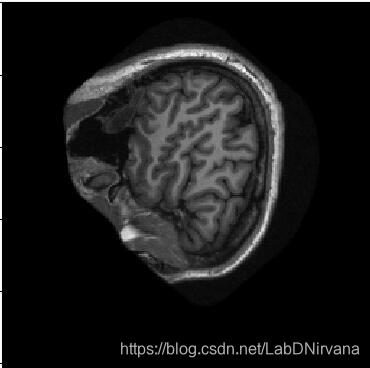

- 原始数据图像: